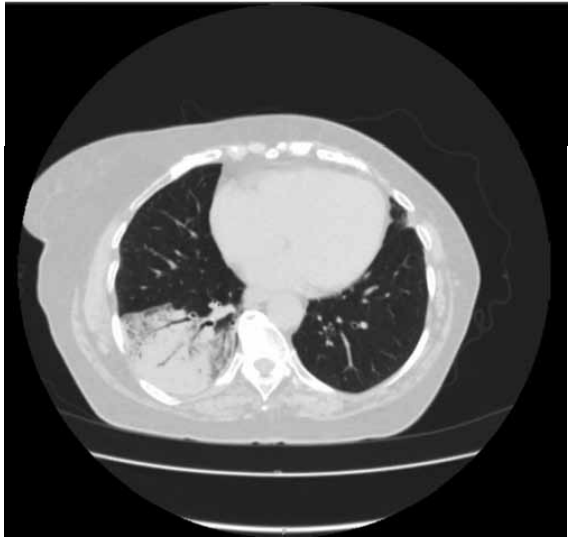

Uma paciente procura auxílio médico com uma queixa de tosse seca há 1 semana. Tem antecedente de hipertensão arterial. Entretanto, há muito tempo não procura controle médico. Ela costuma medir sua pressão arterial por meio de um esfigmomanômetro de pulso. Quando estava normal, não fez uso de hidroclorotiazida 25 mg. Regularmente toma losartana 50 mg à noite e anlodipino 5 mg pela manhã.

Ela realizou uma tomografia computadorizada de tórax:

(Arquivo pessoal; imagem usada com autorização)

Assinale a alternativa correta quanto à prescrição a ser realizada.